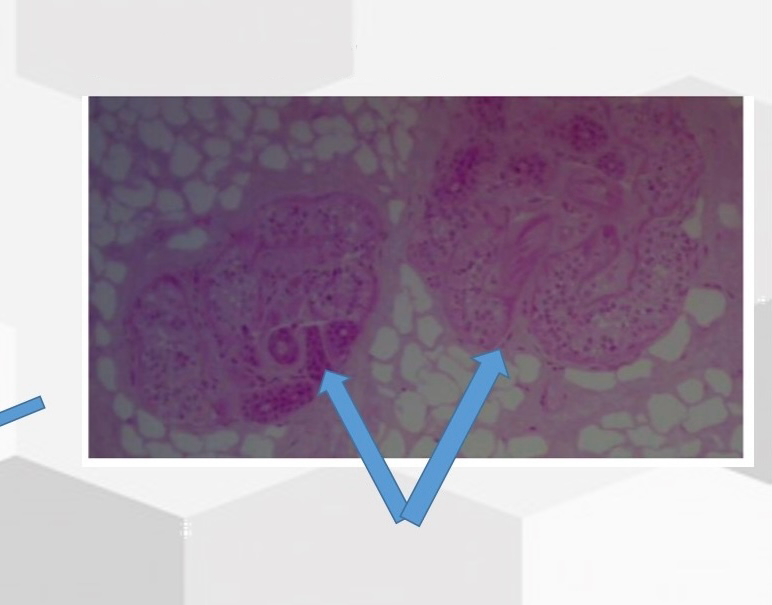

What is this gland

Sebaecous Glands

Name this gland

Eccrine (Sweat) Glands